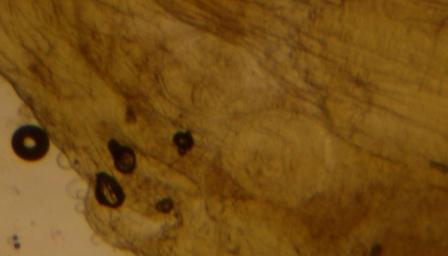

Resaltar que las fotos que aparecen en esta página son de Trichinella observada a la lupa binocular por nuestros alumnos/as y realizadas con una cámara de fotos digital ( para ver fotos de Trichinella al triquinoscopio ir a la visita anteriormente citada ).

1. Se realizan cortes en el músculo ( en este caso de jabalí ) en el sentido en el que van las fibras musculares del tamaño de un grano de arroz o más pequeños.

2. Se depositan sobre una prensa para hacer la muestra más plana y poder observarla.

3. Observar dicha muestra al triquinoscopio o a la lupa binocular.